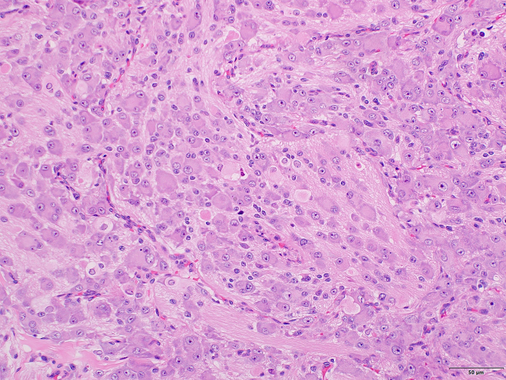

Name this tumour.

Granular cell tumour

Neuroectodermal differentiation

Predilection for the tongue

Granular cytoplasm caused by inactivating mutations in ATP6AP1 or 2 (so can’t break down lysosomes) -> granular ppearance.

Stains: S100 (+), CD68, inhibin, calretinin.

Genetic exceptions: congenital (ginival) granular cell tumour (congenital epulis) - looks simlar, located on gingiva at birth, S100-